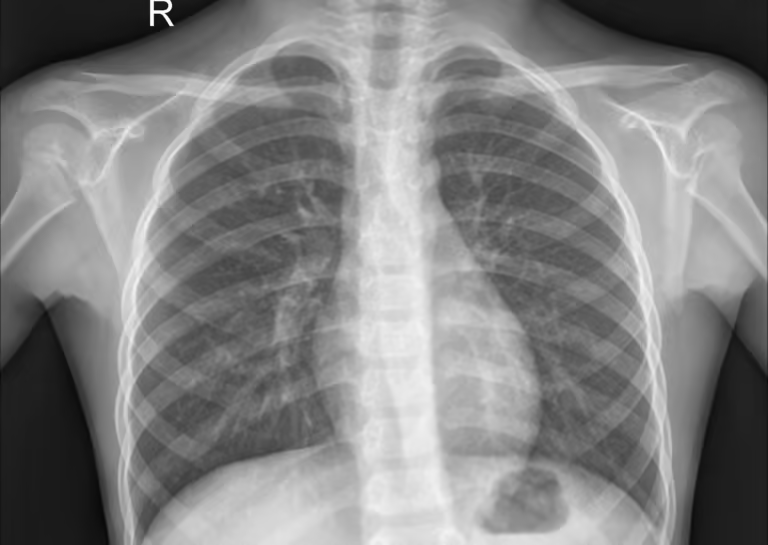

X-ray 胸部肺炎 X 光图像数据集 - 5800 张儿童肺炎检测图像

数据来源源自广州妇女儿童医疗中心 1-5 岁儿童患者回顾性队列,均为常规临床检查 X 光片,经 3 位专家医生评估校验,第 3 位专家专项审查评估集,数据准确性与医疗专业性强。

覆盖范围:含约 5800 张胸部 X 光图像,分为正常、肺炎(细菌性 + 病毒性)两类,按训练集(train)、测试集(test)、验证集(val)三分结构划分,每类文件夹下含对应类别子目录,分类清晰。

数据优势:经过质量控制筛查,剔除低质量、无法读取图像,适配计算机视觉模型训练与自动化诊断系统测试,无需额外筛选即可直接使用。